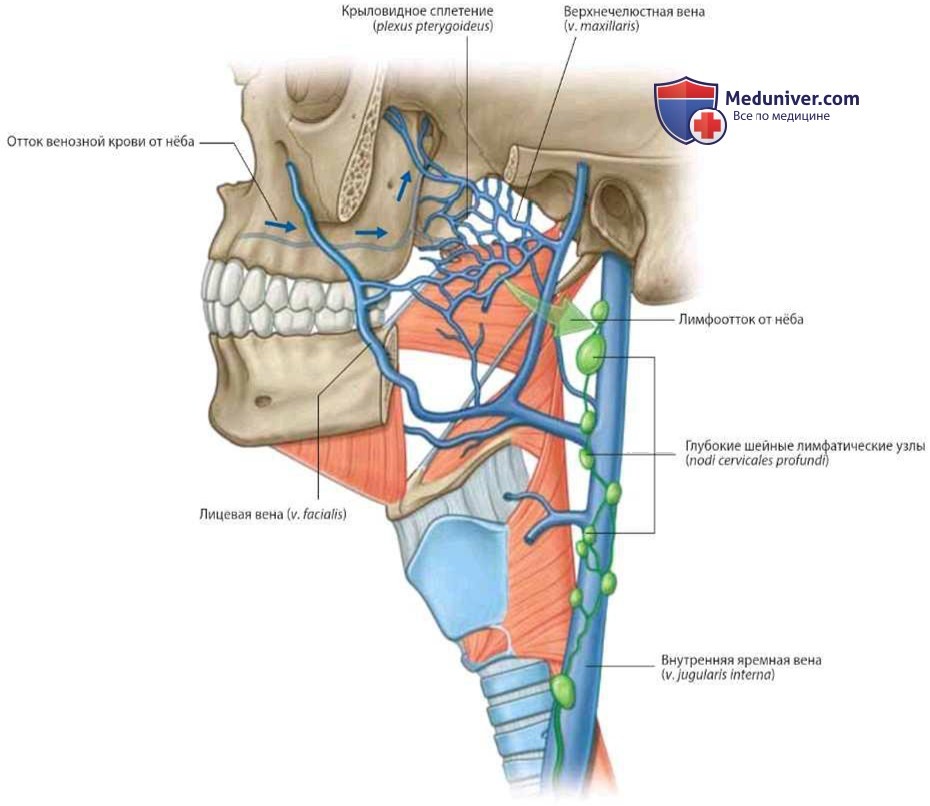

Анатомия внутренней яремной вены: КТ изображения